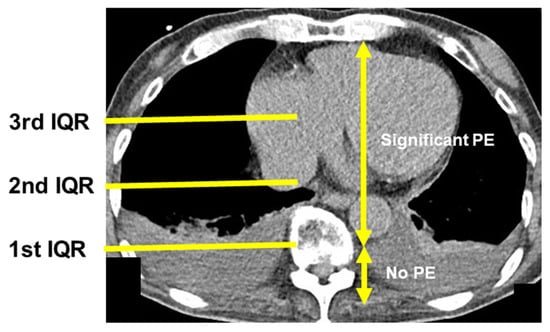

Chest computed tomography images without enhancement were obtained upon admission to semi-quantify the degree of right thoracic PE. An anteroposterior quartile was used to define the degree of PE by a researcher (TI) who was blinded to the results of the ReDS assessment and right heart catheterization at the time of measurement []. The anteroposterior quartile was defined as the most anterior quartile, in which the PE was observed on the axial image above the ipsilateral hemidiaphragm. The PE had the greatest thickness at this slice. Effusion extending beyond the first anteroposterior quartile was defined as significant PE (see Figure 3 as an example of significant PE).

Figure 3.

How to semi-quantify the degree of pleural effusion using chest computed tomography. An anteroposterior quartile of the right lung was used to define the degree of pleural effusion. The anteroposterior quartile was defined as the most anterior quartile in which the pleural effusion was observed on the axial image above the ipsilateral hemidiaphragm. In this study, effusion extending beyond the first anteroposterior quartile was defined as significant pleural effusion. IQR, interquartile range; PE, pleural effusion.

A total of 11 patients had PE between the first and second interquartile lines, indicating the presence of significant PE (PE group). No patients had PE greater than the second interquartile line (Figure 3). The other 48 patients had no PE or PE below the first interquartile line, indicating no significant PE (no-PE group). Patients in the PE group had higher plasma B-type natriuretic peptide levels and ReDS values (p < 0.05 for both; Table 1). Most of the other variables were not significantly different between the two groups (p > 0.05).